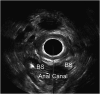

Total pelvic floor ultrasound is used for the dynamic assessment of pelvic floor dysfunction and allows multicompartmental anatomical and functional assessment. Pelvic floor dysfunction includes defaecatory, urinary and sexual dysfunction, pelvic organ prolapse and pain. It is common, increasingly recognized and associated with increasing age and multiparity. Other options for assessment include defaecation proctography and defaecation MRI. Total pelvic floor ultrasound is a cheap, safe, imaging tool, which may be performed as a first-line investigation in outpatients. It allows dynamic assessment of the entire pelvic floor, essential for treatment planning for females who often have multiple diagnoses where treatment should address all aspects of dysfunction to yield optimal results. Transvaginal scanning using a rotating single crystal probe provides sagittal views of bladder neck support anteriorly. Posterior transvaginal ultrasound may reveal rectocoele, enterocoele or intussusception whilst bearing down. The vaginal probe is also used to acquire a 360° cross-sectional image to allow anatomical visualization of the pelvic floor and provides information regarding levator plate integrity and pelvic organ alignment. Dynamic transperineal ultrasound using a conventional curved array probe provides a global view of the anterior, middle and posterior compartments and may show cystocoele, enterocoele, sigmoidocoele or rectocoele. This pictorial review provides an atlas of normal and pathological images required for global pelvic floor assessment in females presenting with defaecatory dysfunction. Total pelvic floor ultrasound may be used with complementary endoanal ultrasound to assess the sphincter complex, but this is beyond the scope of this review.